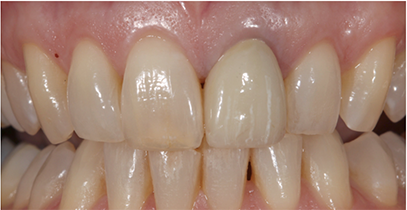

A 60-year-old female presented upon referral from her general dentist for prosthodontic treatment when she requested a new full-coverage crown restoration for tooth #9. She fractured the tooth participating in gymnastics as a child. The tooth was initially restored with composite resin, but when it became discolored, endodontic therapy followed by placement of a cast post, core and crown was performed. The ceramic on the mesial-incisal portion of the crown had fractured (Fig. 1), so the patient reported that it was finally time to replace it.

Fig. 1 Fig. 2

The patient also reported that she was never happy with the restoration, and she also was unhappy with the incisal chipping on tooth #8. Since she was about to embark on a new career, she wanted a smile she felt confident about.